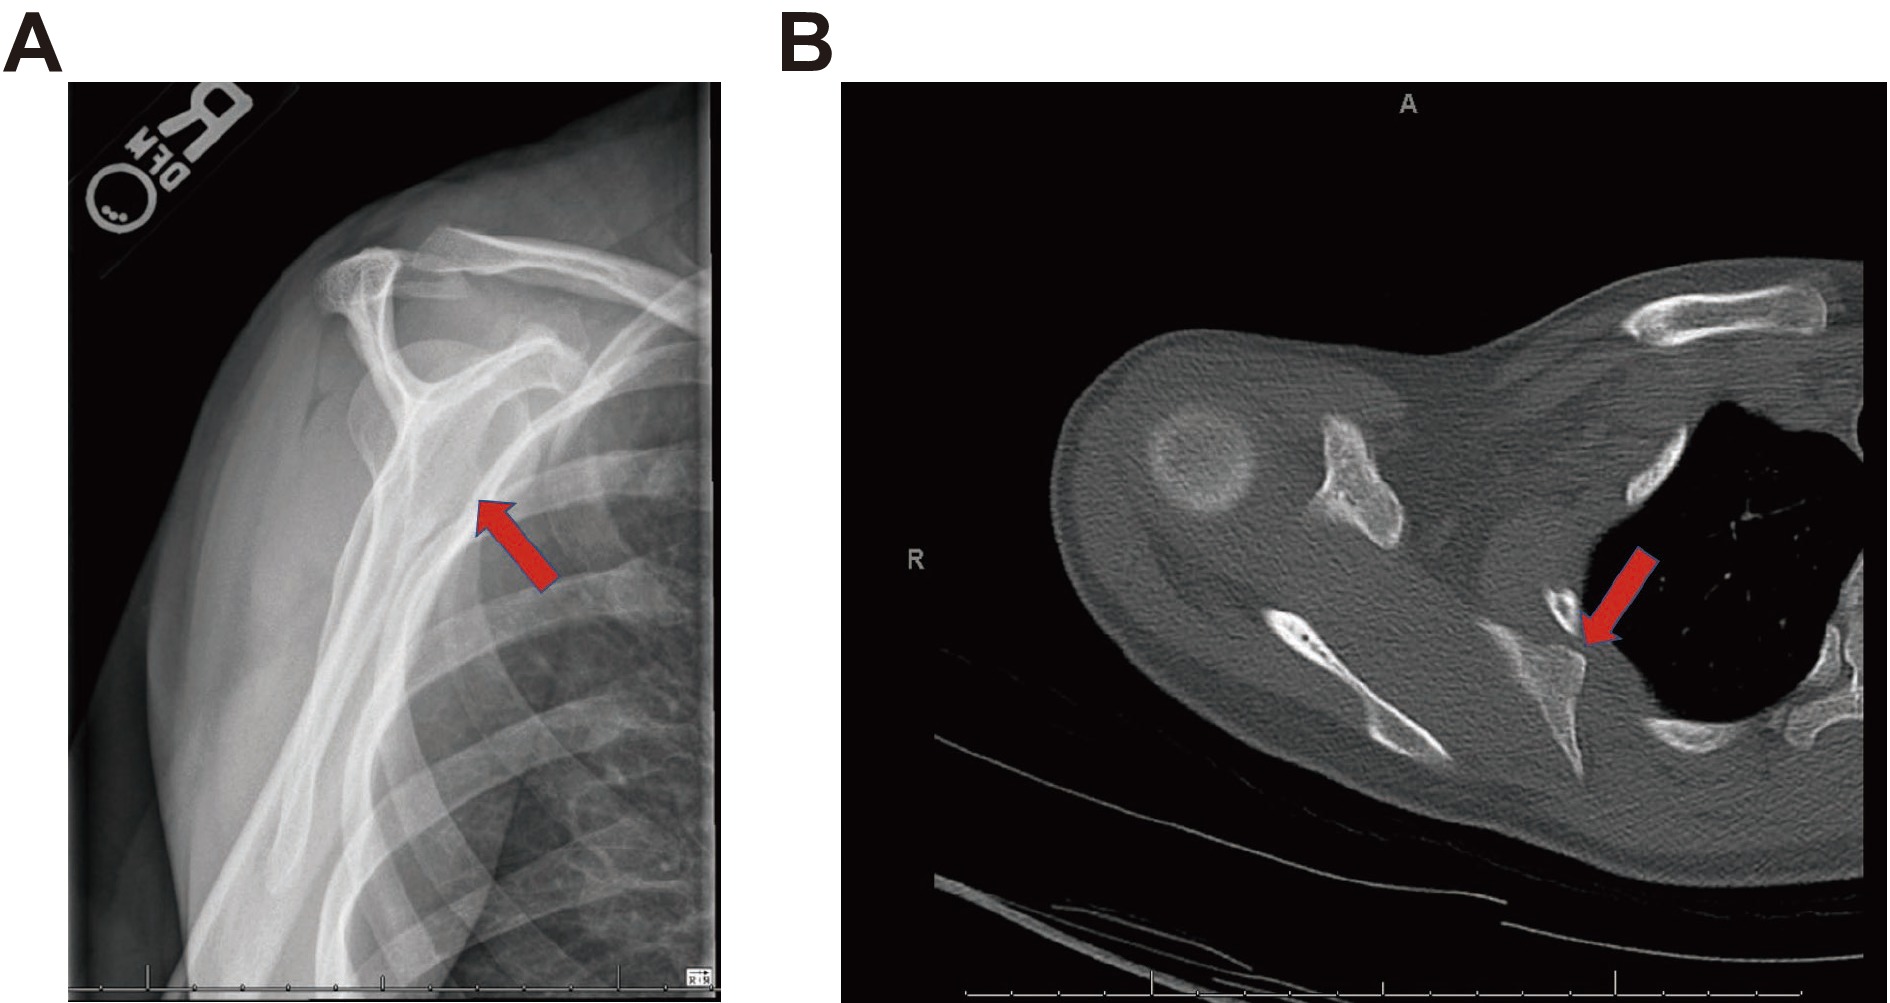

A 26-year-old female, who had a past medical history significant for hereditary multiple exostoses, multiple hereditary osteochondromas, and functional neurological symptom disorder, presented to the orthopedic oncology service with ongoing right shoulder pain associated with a snapping sensation of the scapula (Fig. 1). The patient had a significant past surgical history that included prior excision of multiple lower extremity osteochondromas starting in 2007. Of note, surgical resection of the left scapula and proximal humerus osteochondroma occurred during the prior year with post-surgical placement of an interscalene block. Because of persistent right upper extremity pain with movement and a failed conservative therapy, the surgical team planned for an excision of the scapular body osteochondroma with local infiltration. Of note, the patient had significant drug allergies to multiple pain medications, including dilaudid, morphine, oxycodone, and tramadol, that cause hives and dyspnea. A local anesthetic infiltration by the surgical team consisting of 25 mL of 0.25% bupivacaine was injected into the skin and deep muscle. Prior to block placement in the post-anesthesia care unit, the patient reported a pain score of 9/10 on the numeric rating scale.